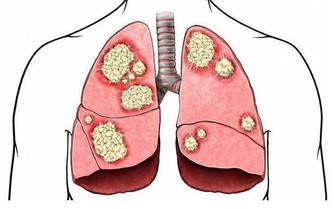

眾所周知,愛滋病是一個危害性極大的傳染病,是由於感染上愛滋病病毒(HIV)而引起的,死亡率很高。有數據表明,全球至少已有3千多萬人死於愛滋病,由此可見愛滋病威力之大。

艾滋病傳播的途徑主要是:與感染者的血液、乳汁、精液、陰道分泌物等多種體液發生交換。

唾液、淚液、汗液、尿液、糞便中的HIV含量很低,基本不能傳播HIV。